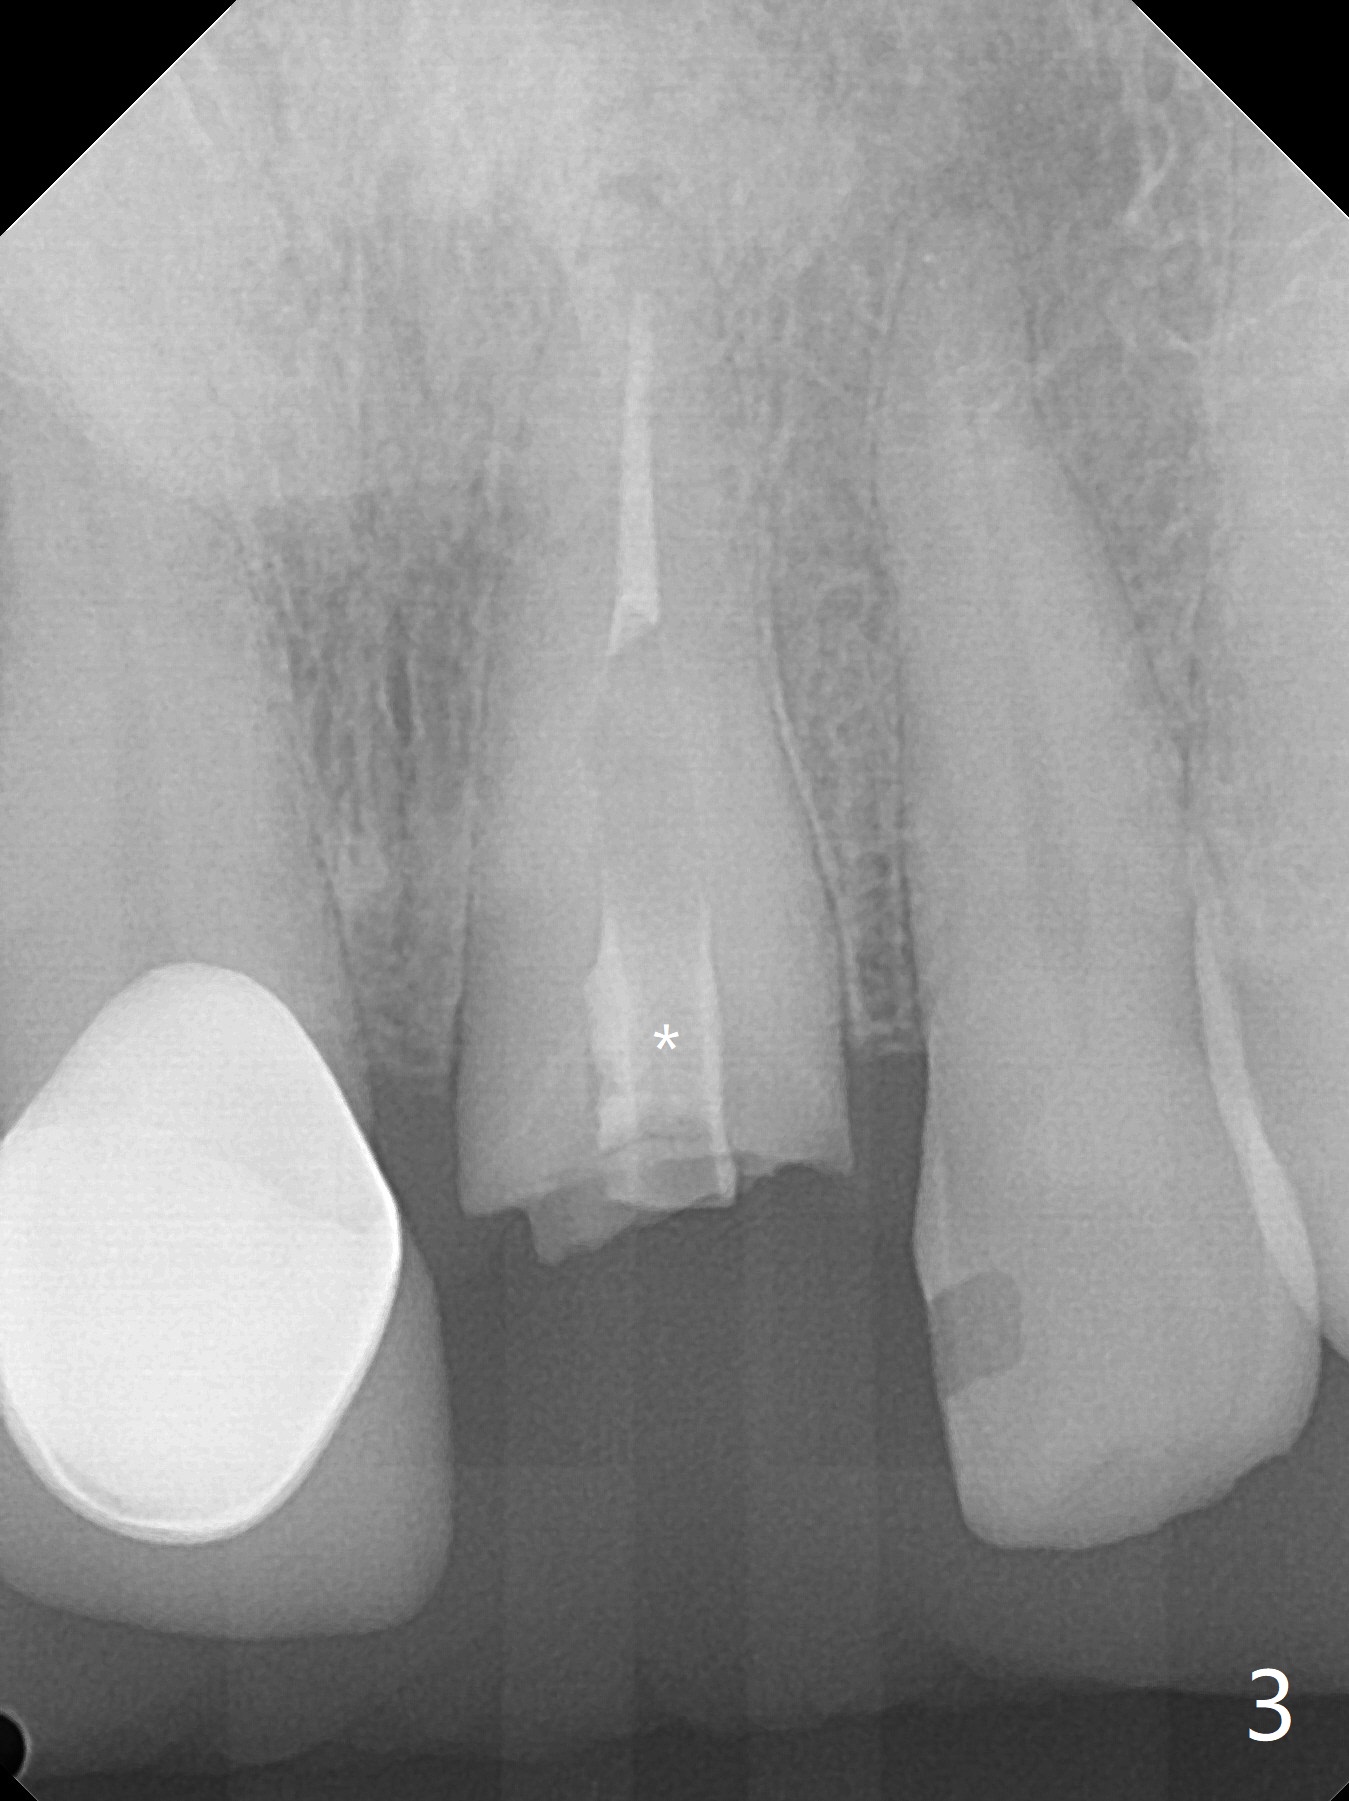

A 58-year-old man fractures the tooth #9 equigingival (Fig.1) and fiber post (Fig.2,3 *). The marginal gingiva is erythematous and edematous (Fig.1 *), suggesting biologic width violation. Redo crown would aggravate the issue. In addition, the mesiobuccal root of the tooth #14 has vertical fracture (Fig.4,5), evidence of heavy mastication. In fact the tooth #13 was also fractured apparently due to heavy occlusion before extraction. It is the best to extract the tooth #9 for implant (Fig.6), or tissue-level (3.5x14 or 17 mm).